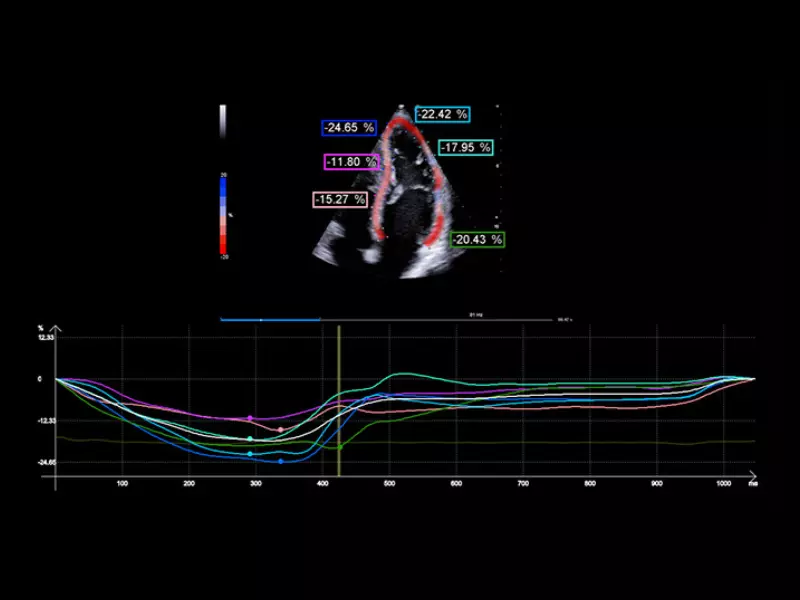

MyLab™9 Platform - XStrain4D technology for volumetric heart assessment by coronary territories

MyLab™9 Platform - XStrain4D technology for volumetric heart assessment by coronary territories

MyLab™9 Platform - XStrain™ 2D speckle tracking technologies for global and regional function

MyLab™9 Platform - XStrain™ 2D speckle tracking technologies for global and regional function